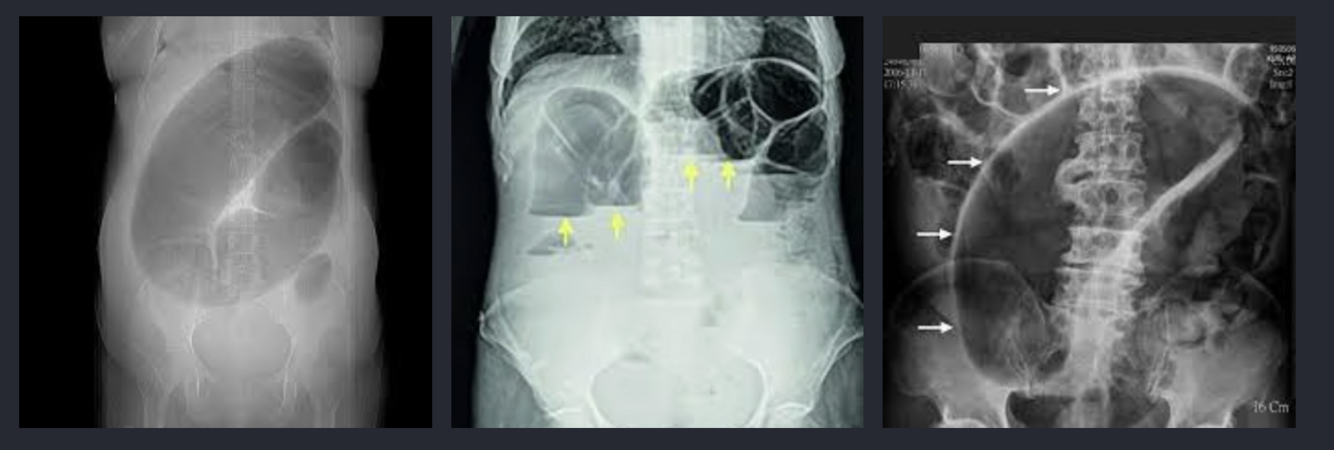

Rx simple de abdomen: imagen en “grano de café”, patrón clásico de sigmoides

TAC abdominopélvica con contraste: “signo del remolino”, torsión de mesenterio

La radiografía simple AP de pie y de cúbito es el estudio inicial de elección

Grano de café y remolino